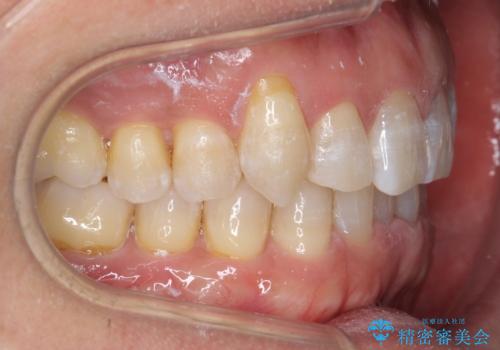

八重歯と下の歯のがたつき マウスピースで

- 右上の犬歯が目立つのが気になる、下の歯並びも治したいとのことで来院。

歯を抜かずに少し削って小さくして並べました。

並びも良くなり、患者様にも喜んでいただきました。

右上の犬歯の歯肉退縮自体は進行する可能性をお伝えしておりましたが、特に変化なく治療できました。

歯肉退縮につきましては、歯ぐきの移植を提案しましたが特に希望されませんでした。